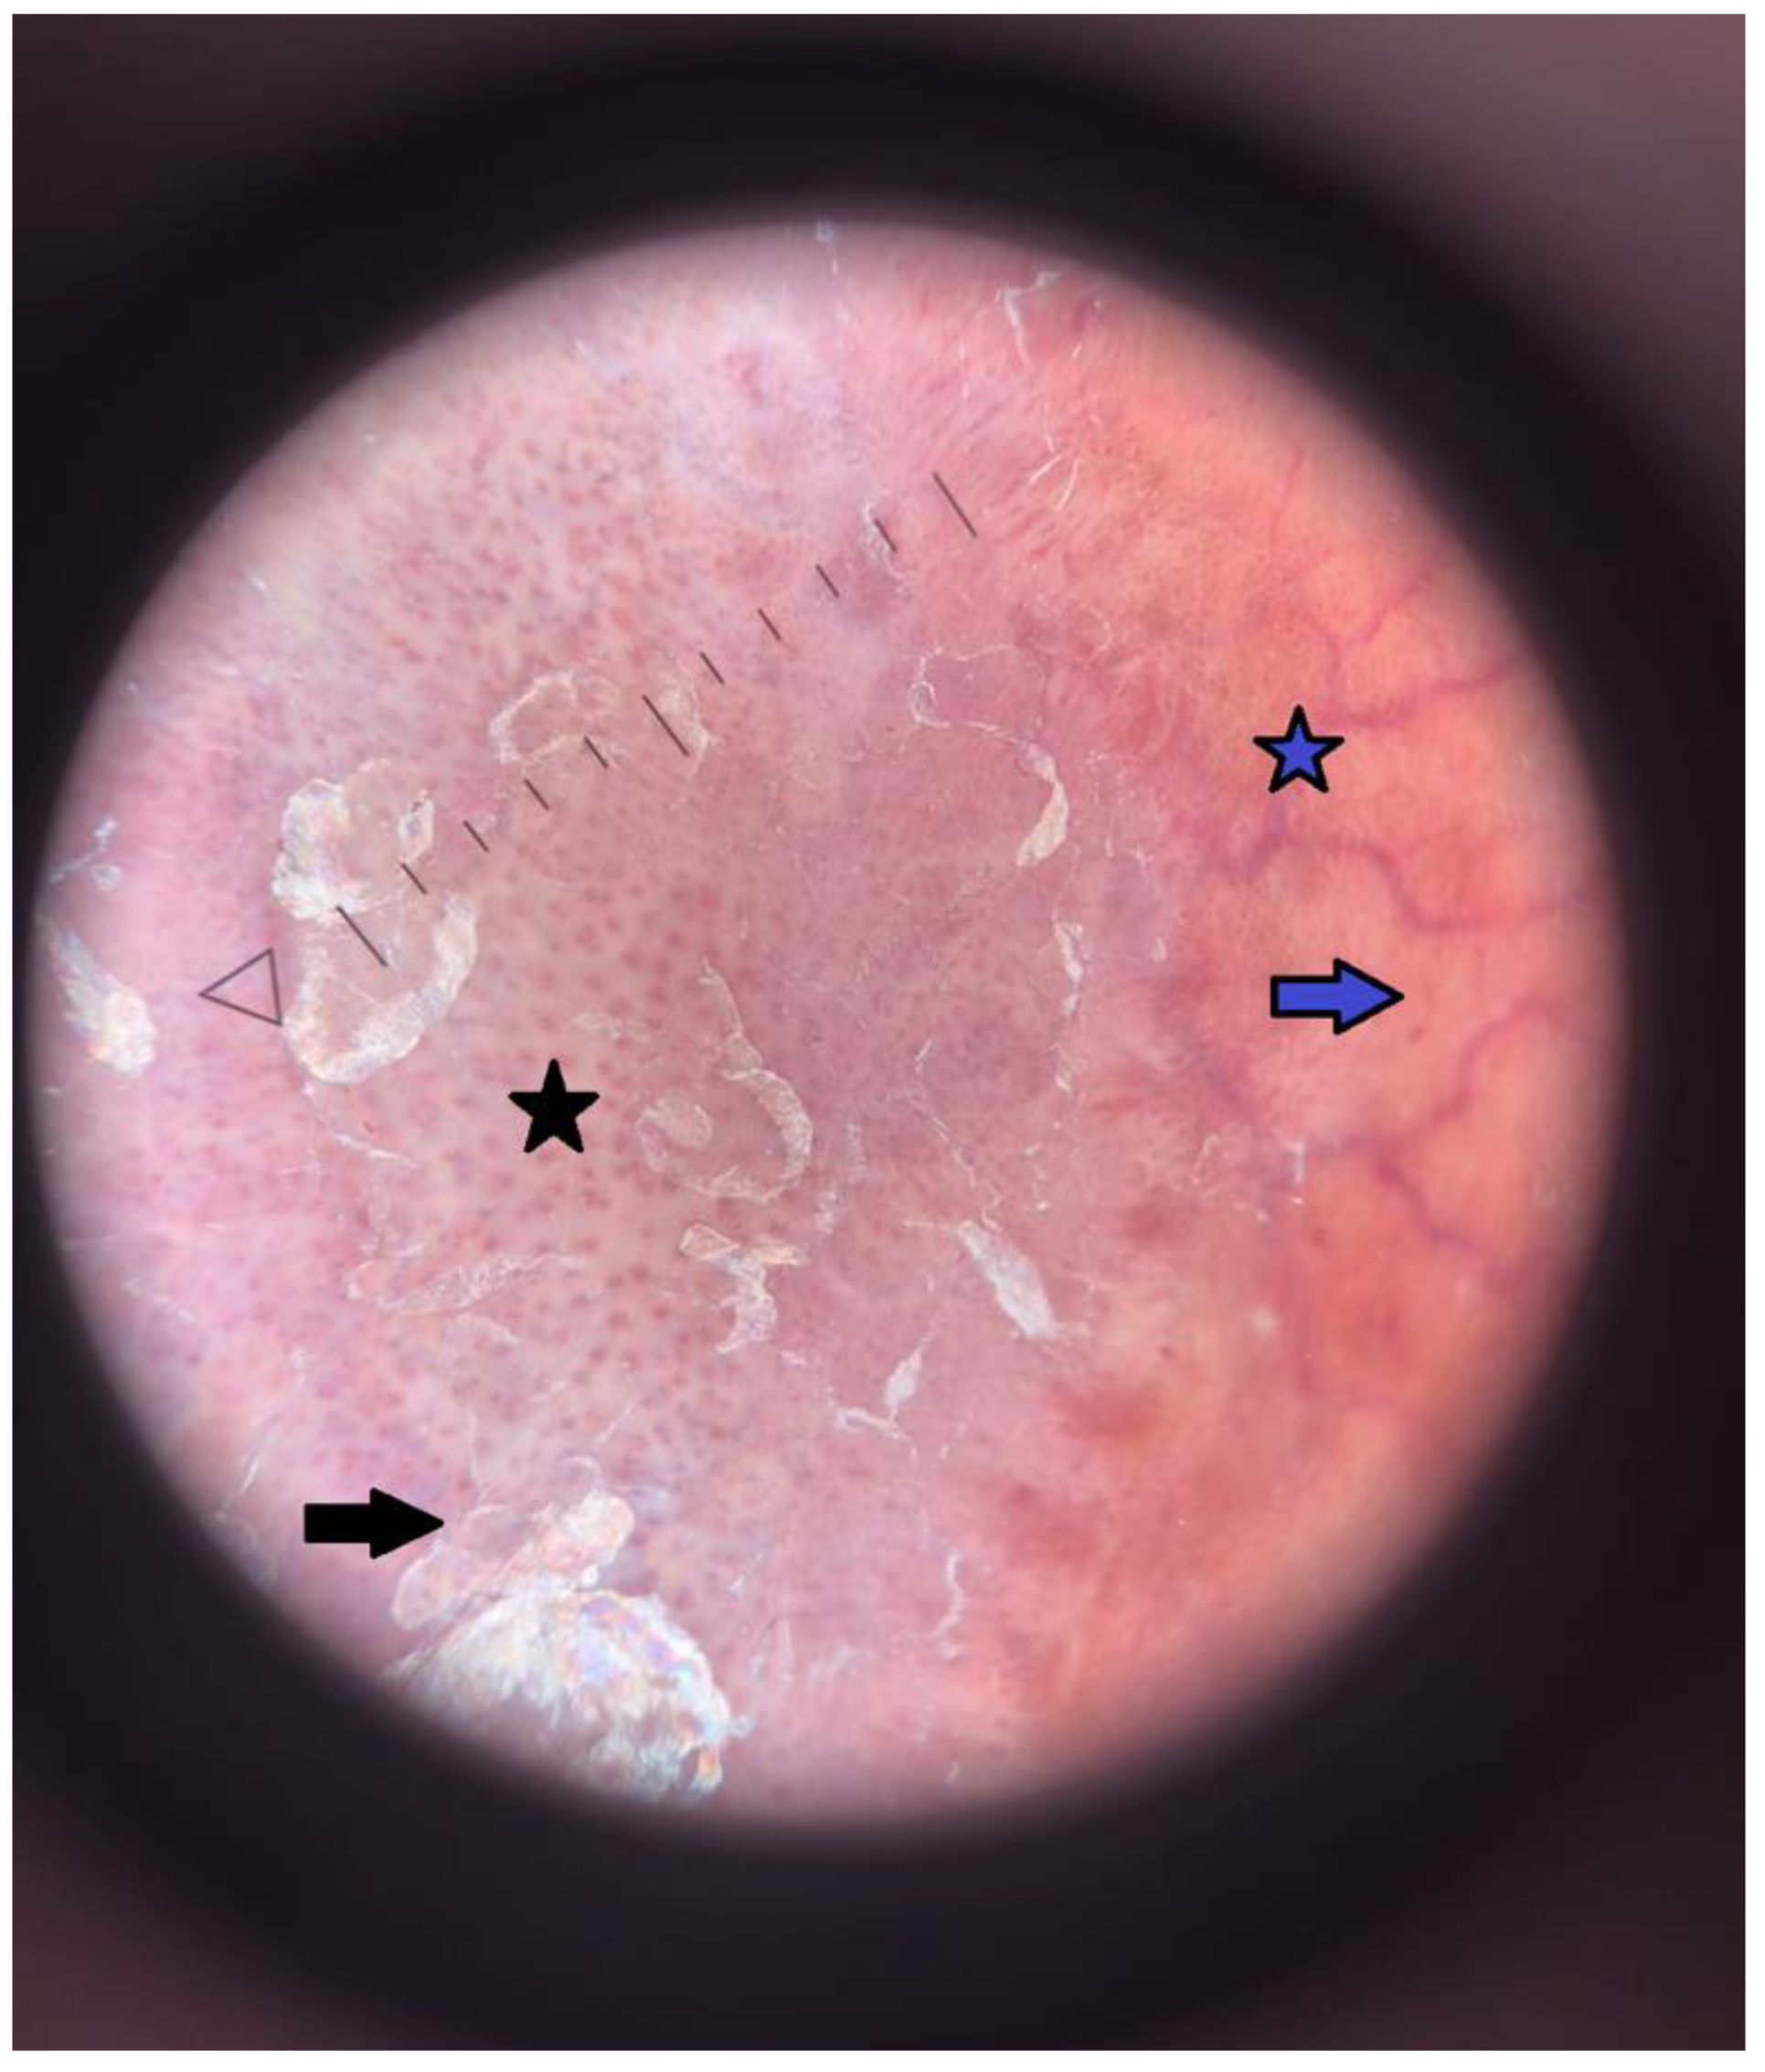

An 18-year-old male with a complex medical history of psoriasis, T1DM, and essential hypertension (HTN) was admitted to the Department of Pediatrics, Endocrinology, Diabetology with Cardiology Divisions for evaluation and to determine a further individualized management strategy. He was first diagnosed with type 1 diabetes mellitus and psoriasis in 2015, at the age of nine. In 2020, essential hypertension was identified, and ramipril at 10 mg once daily was introduced, although adherence remained inconsistent. In February 2022, the patient was hospitalized for control tests and re-education due to persistently elevated HbA1c levels and poorly optimized insulin dosing. On admission, skin examination revealed extensive erythematous and desquamative plaques on the scalp, forehead, trunk, and the anterior parts of the shins (Figure 1). The plaques on the shins were atrophic, and a superficial ulceration on the left leg was observed. Dermoscopy of the lesions revealed an orange background and multiple branching vessels, which led to a diagnosis of necrobiosis lipoidica (NL) coexisting with psoriasis vulgaris (Figure 2). The patient’s metabolic profile was characterized by a height of 187.5 cm, a weight of 123 kg, and a body mass index (BMI) of 34.9 kg/m2, placing him above the 97th percentile for his age. His waist circumference measured 115 cm, which exceeds the 97th percentile for 18-year-old males, indicating marked central adiposity. This yielded a waist-to-height ratio (WHtR) of approximately 0.6, placing him in the moderate- to high-risk category for obesity-related cardiometabolic complications [1]. Blood glucose monitoring revealed significant fluctuations, ranging from 90 to 400 mg/dL. His HbA1c level was elevated at 11%, reflecting suboptimal diabetes management and placing him at high risk both for acute and chronic complications of T1DM [2]. His blood pressure was controlled with antihypertensive therapy, recorded at 120/70 mmHg under treatment with ramipril. However, 24-hour ambulatory blood pressure monitoring revealed the following complex pattern: 32.7% of systolic and 2.0% of diastolic blood pressure readings were above reference values during the day. At night, 12.5% of systolic and 0% of diastolic values exceeded reference levels. Notably, a blunted nocturnal dip in blood pressure was observed, with a mean arterial pressure (MAP) reduction of only 6.7%, indicating a suboptimal nocturnal decline in blood pressure [3]. Laboratory analysis revealed triglyceride (TG) levels of 84 mg/dL and HDL cholesterol levels of 64 mg/dL. While this TG level is within normal parameters, the HDL level, although not critically low, is suboptimal for cardiovascular health, particularly in the context of T1DM and obesity [4]. To provide a clearer diagnostic framework, Table 1 summarizes how the patient meets the criteria for metabolic syndrome according to the most commonly used pediatric and adolescent definitions [5,6,7].